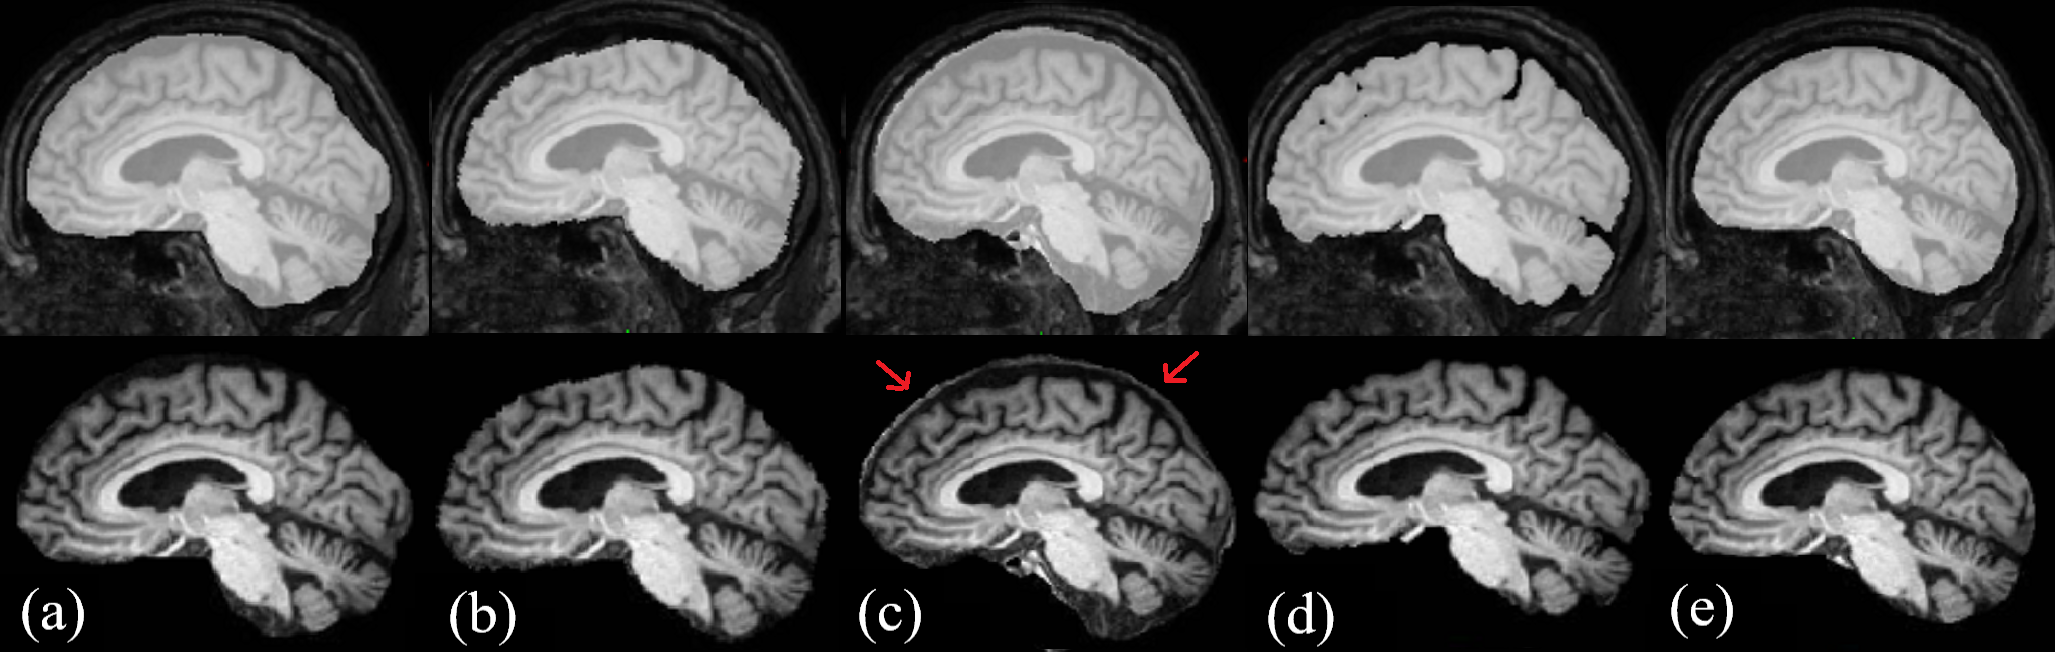

For qualitative analysis, we performed a visual inspection of results from all methods. Our analysis shows that the proposed method is highly consistent in the amount of CSF included in the segmentations. The method also demonstrates high robustness towards pathologies and movement artefacts, as demonstrated in Figure 2, where MONSTR and Synthstrip (without CSF) remove a significant amount of brain tissue, while the proposed method better preserves brain tissue. In some cases, MONSTR removed a large amount of tissue in the brainstem, which is often critical to subsequent analysis, while our model correctly preserved it. Figure 3 shows an example from the held-out test set, showcasing Synthstrip’s oversegmentation, where it occasionally includes the meninges around the brain tissue. This inconsistent inclusion of the meninges can be problematic for subsequent image processing. An example from the external indepdendent test set can be seen in Figure 4.

![]() |